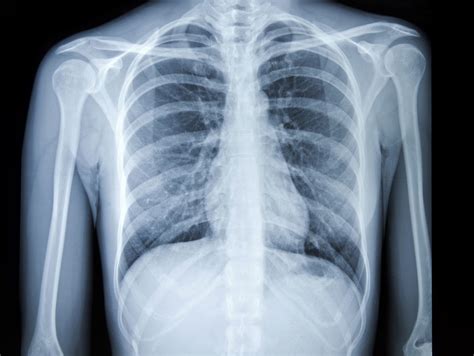

Common Findings in a Normal Chest Ray

A Normal Chest Ray typically reveals the following structures and conditions:

Structure/Condition Description

Lungs Clear lung fields with no signs of infection, inflammation, or tumors.

Heart Normal size and shape, with no signs of enlargement or fluid accumulation.

Ribs and Spine Intact bones with no fractures or abnormalities.

Diaphragm Normal position and movement.

Pleural Space No fluid or air accumulation.

Interpreting a Normal Chest Ray

Interpreting a Normal Chest Ray involves examining the images for any abnormalities. Radiologists look for signs of:

• Lung Conditions: Pneumonia, lung cancer, or emphysema.

• Heart Issues: Enlarged heart, fluid around the heart, or heart failure.

• Bone Abnormalities: Fractures, tumors, or infections in the ribs or spine.

• Other Structures: Enlarged lymph nodes, pleural effusions, or foreign objects.